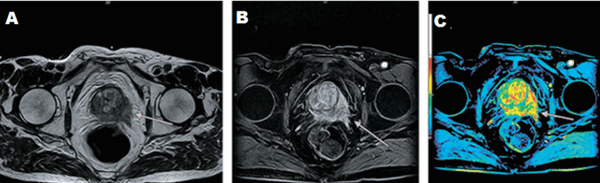

А - магнитно-резонансная томограмма демонстрирует неровность контура капсулы левой доли простаты с распространением мягкотканного компонента за ее пределы (стрелка), Т2 ВИ. В - изображение после динамического введения гадолиния. С - после обработки компьютерной программой - явное усиление интенсивности МР-сигнала в зоне патологии, типичное для неопластического перерождения